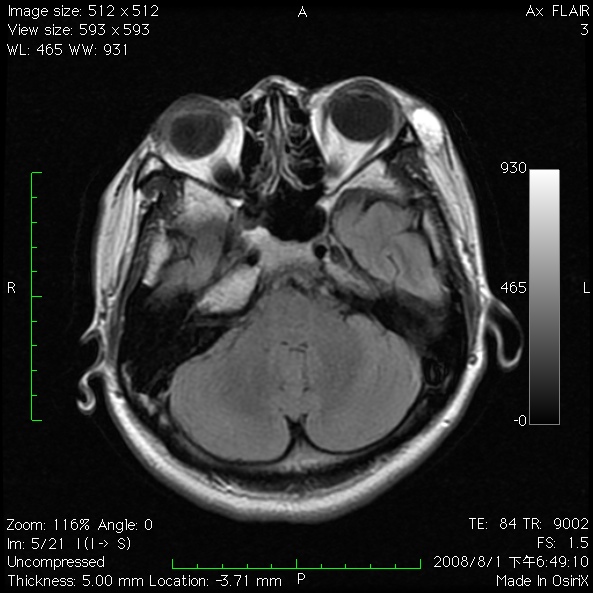

This 26-year-old healthy lady noted a mass between left lateral at lateral orbital  rim and left ear. The mass is soft, painless with blur margin. This mass did not result in any significant visual disturbance nor neurological sign. She had ever visited our ophthalmologist and MRI survey in 2008 revealed a well-defined, encapsulated, heterogeneous cystic mass in T1 sequence and hypo-intensed mass in fat suppression sequence. The mass was about 3*2cm in size located lateral to left orbital rim next to temopralis muscle, suspecting lipoma or other benign lesion. She did not took advanced intervention till this month. For better aesthetic and healthy issue she was admitted for surgical intervention.